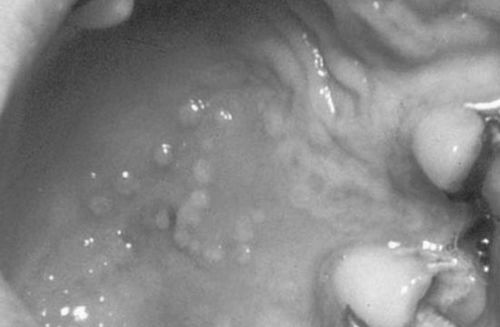

Середня форма тяжкості дається взнаки інтоксикацією організму із загальною слабкістю і сонливістю, збільшенням лімфовузлів і ангіною. Хворі скаржаться на різкий стрибок температури до 39 °, запаморочення і головний біль. У роті з'являються рідинні бульбашки і білястий наліт. Сверблячкою елементи створюють дискомфорт, ясна кровоточать. Прийом їжі не може через хворобливості, слиновиділення підвищений. Кількість виразок досягає 25 штук.

На фото показані зовнішні ознаки герпетичного стоматиту у дорослих.